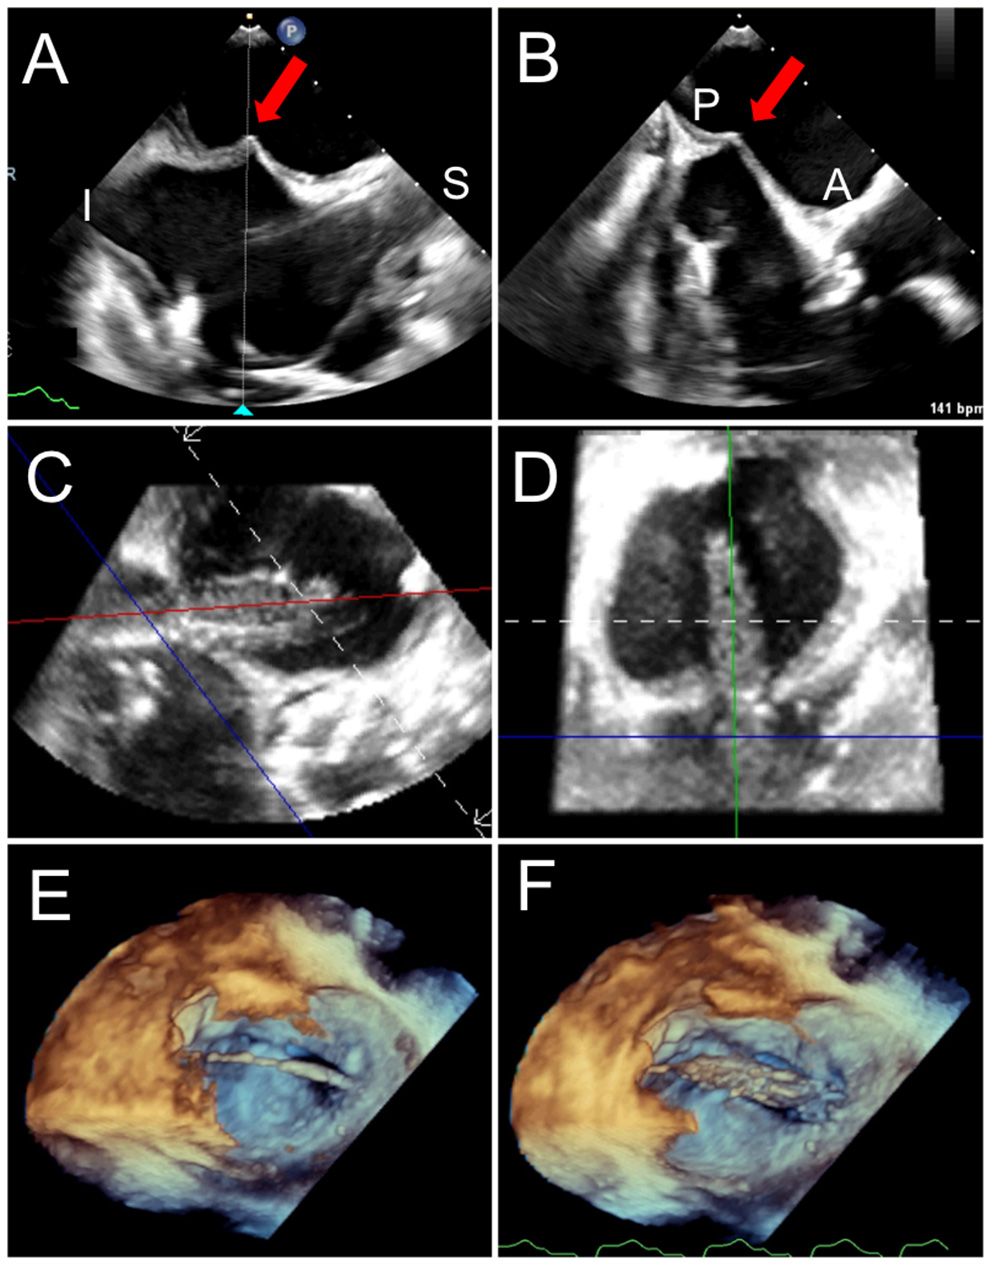

The ideal and less invasive approach for TMVR is via transseptal puncture; in addition to being preferred by patients, it may allow for improved LV function and lower complications as compared to a transapical approach (37, 45). The transseptal approach, though technically more challenging, can be used for the balloon-expandable Sapien 3 valves (Edwards Lifesciences, Irvine, CA) for ViV, ViR, and ViMAC, as well as the investigational devices for valve in native annulus implantation, including CardiAQ-EVOQUE and Valtech CardioValve (Edwards Lifesciences, Irvine, CA), Cephea (Abbott Structural, Santa Clara, CA) and HighLife (HighLife Medical, Irvine CA) (36, 37, 46–49). After venous and arterial access is obtained, the interventionalist advances a transseptal needle and sheath over the wire into the superior vena cava, then slowly withdraws it into the right atrium under TEE guidance, until tenting of the septum is noted. The needle position is assessed in the mid-esophageal bi-caval view (superior-inferior) and short-axis view (anterior-posterior), and height can be confirmed in a 4-chamber view. Transseptal puncture for TMVR is usually performed in the infero-posterior portion of the fossa ovalis, or the ideal position as determined by pre-procedural CCTA analysis, which may be projected to real-time TEE via fusion imaging (50). Orthogonal bi-plane imaging and live 3D imaging can simultaneously display all four rims of the fossa ovalis and serve for confirmation (Figures 6A,B). Fusion of real-time TEE and fluoroscopy can further facilitate transseptal sheath positioning. Once the ideal puncture site is achieved, the needle and sheath will be advanced into the LA under continuous TEE visualization. The transseptal sheath is subsequently exchanged by the specific device sheath. A pigtail catheter is advanced over a guidewire across the mitral valve toward the LV apex and subsequently exchanged by a curved stiff wire. Due to the larger dimensions of the TMVR valves and delivery system (as compared with edge-to-edge repair), a balloon atrial septostomy is necessary and performed under TEE and fluoroscopic guidance (Figures 6C–F, Supplementary Video 1).

Figure 6

Trans-septal puncture and septostomy for TMVR. A transseptal needle is seen tenting the interatrial septum (red arrows), best assessed utilizing biplane TEE imaging in the bi-caval (superior-inferior, A) and short-axis (anterior-posterior, B) views to confirm positioning in the inferior and posterior aspect of the fossa ovalis. After a successful transseptal puncture, a balloon is advanced over a stiff wire, and proper positioning across the septum can be verified utilizing live 3D MPR (C,D). (E) The balloon is visualized in a 3D zoom volume-rendered image from the left atrial perspective. (F) The balloon is inflated for atrial septostomy in order to later accommodate the large crimped TMVR device. Supplementary Video 1 illustrates balloon inflation for atrial septostomy, as seen from the left atrium.